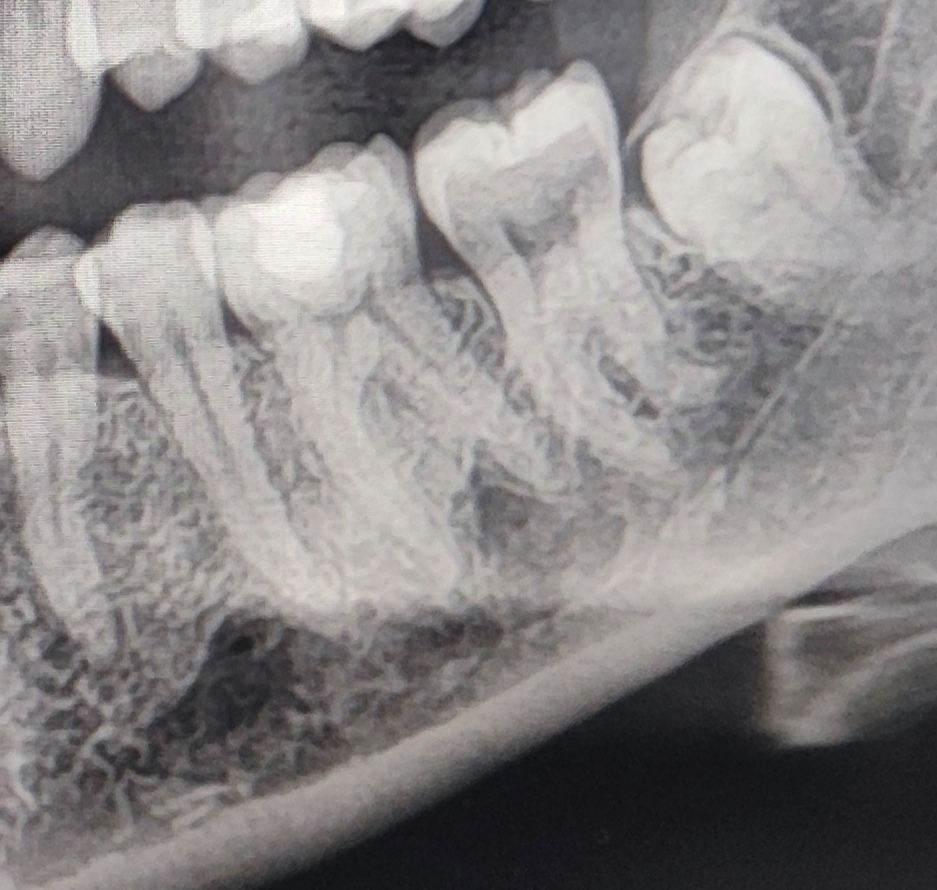

takto mi rastie dolna 8, dva mesiace trpim tlakom a bolestami zubov, cize styri zuby rozvrtane, posledne dni citim, ze sa pohla 8, citim, ze sa tlaci cez dasno, je tesne pod nim, vkuse mi tam zavadzia lice a kusem si do nho, muz ma ukludnuje, ze to prejde, ale nema ako, ked je uz skoro von, nemam miesto na nu, uz dost, ze mam spodne zuby krive, mam sa objednat na vytrhnutie? Liecia mi hornu 7 zapal korenov a este toto mam teraz ako bonus 😥

@patus_2 no zubarka nevedela odkial je problem, zobudila som sa s bolestou sanky, takze rozvrtane 4 zuby, ale v jednom bol ozaj problem, ale ta ostatna bolest moze byt z osmicky lebo ma rozboli sanka a potom prestane, ja mam von len jednu 8, inak obe dolne mam tak, len tuto asi o 3 mm uz vyssie